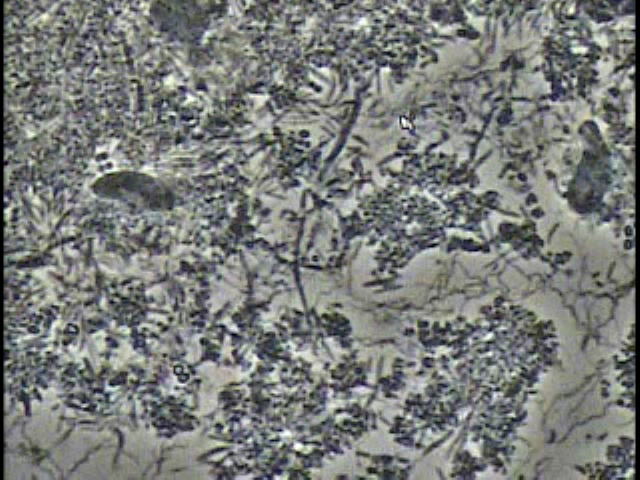

歯周病はいわば「骨の病気」です。

骨の病気ですので、診断にはまずはレントゲンの撮影が必要です。

もっと詳しく診断するにはCT装置による撮影を行い、

歯を支えている骨(歯槽骨)や顎の骨、

顎関節の状態まで確認することが必要になります。

歯周病はいわば「骨の病気」です。

骨の病気ですので、診断にはまずはレントゲンの撮影が必要です。

もっと詳しく診断するにはCT装置による撮影を行い、

歯を支えている骨(歯槽骨)や顎の骨、

顎関節の状態まで確認することが必要になります。